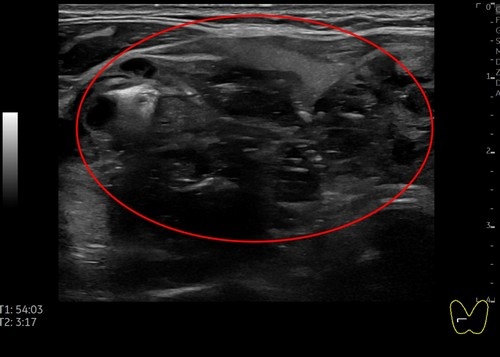

日前,一位51歲女性病人因頸部中間部位腫大來花蓮慈濟醫院影像醫學部施于泰醫師門診,經以超音波檢查,發現右邊有一5.15公分結節,另一個結節靠近甲狀腺峽部約2.99公分;在以細胞學穿刺檢查後為良性結節。病人在接受甲狀腺消融術治療後,隔天即出院恢復正常生活,且一週後已明顯消腫,無副作用發生。

右圖:女病患右側甲狀腺5.15公分結節微波消融後超音波影像。(施于泰提供)